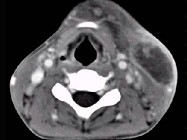

- 单项选择题男性,67岁, 颈部出现疼痛性肿块半年余,CT扫描如图所示, 最可能的诊断是 ( )